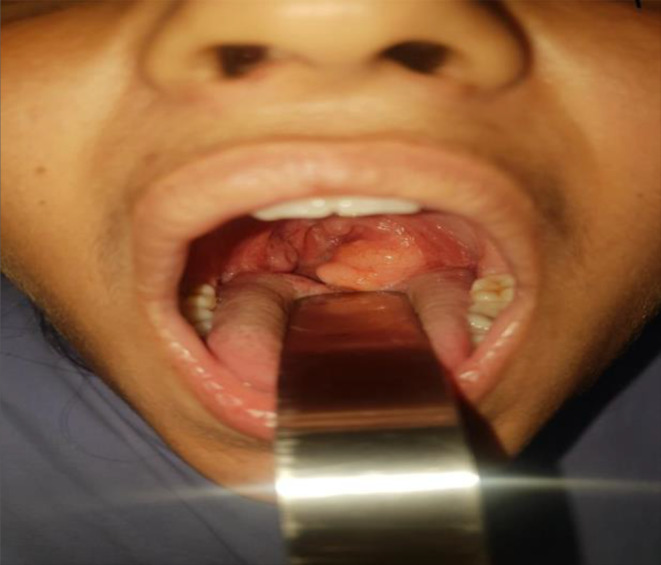

Patient was admitted in ENT department and his baseline as well as specific investigations were ordered. In the same manner, the observations like blood pressure (BP), heart rate (HR) and Temperature (Temp) was normal at the time of admission and remain so through out the stay in hospital. Similarly, the baseline investigations were also within the reference ranges. Upon detailed examination of the oral cavity, an irregular mass measuring 2 cm x 3 cm was observed as shown in Fig. 1. It was protruding from the left palatine tonsil and extending across the midline. The mass was mobile and non-pulsatile. Examination of the nose and nasal cavity revealed no abnormalities, and the cervical lymph nodes were not enlarged.

Fig. 1.

Showing the left tonsillar mass measuring 2 cm x 3 cm, extending from the left tonsillar fossa to the oropharynx